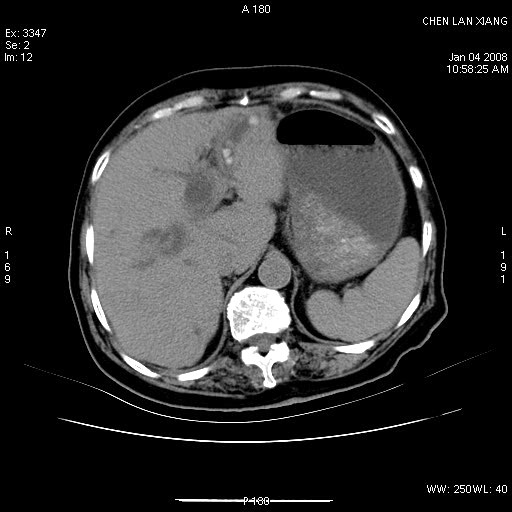

女,76岁,腹痛3-4天,b超示:肝内实性肿物,胆囊强回声,胆总管扩张.

考虑:1、胆总管下端结石伴梗阻性肝内外胆管扩张(肝左叶外侧段肝内胆管多发结石、胆管炎);

2、肿囊癌累及肝,不除外 黄色肉芽肿性胆囊炎。

1 胆总管末端结石伴肝内胆管结石,肝内外胆管扩张。2 胆囊扩大,胆囊壁不规则增厚,内见软组织密度影。考虑:慢性胆囊炎,不除外胆囊癌!

胆囊密度增高,增强后周边肝组织及胆囊窝下部周边软组织延时性不规则强化.然胆囊壁未见明显不规则增厚及肿块.左侧肝内胆管及胆总管下段结石伴胆系扩张.

考虑;胆囊炎(黄色肉芽肿性胆囊炎?),左侧肝内胆管及胆总管下段结石.

ct所见:1、 肝内胆管结石,肝内外胆管扩张。低位胆道梗阻,胆总管下端结石;2 胆囊扩大,胆囊壁不规则增厚

考虑:胆总管下端结石并肝内外胆管扩张,肝内胆管结石;

标题: 肝右叶病灶

胆囊癌侵犯肝右叶?

1)胆囊癌伴肝脏转移。2)胆总管下端结石、肝内胆管结石伴肝内外胆管扩张。